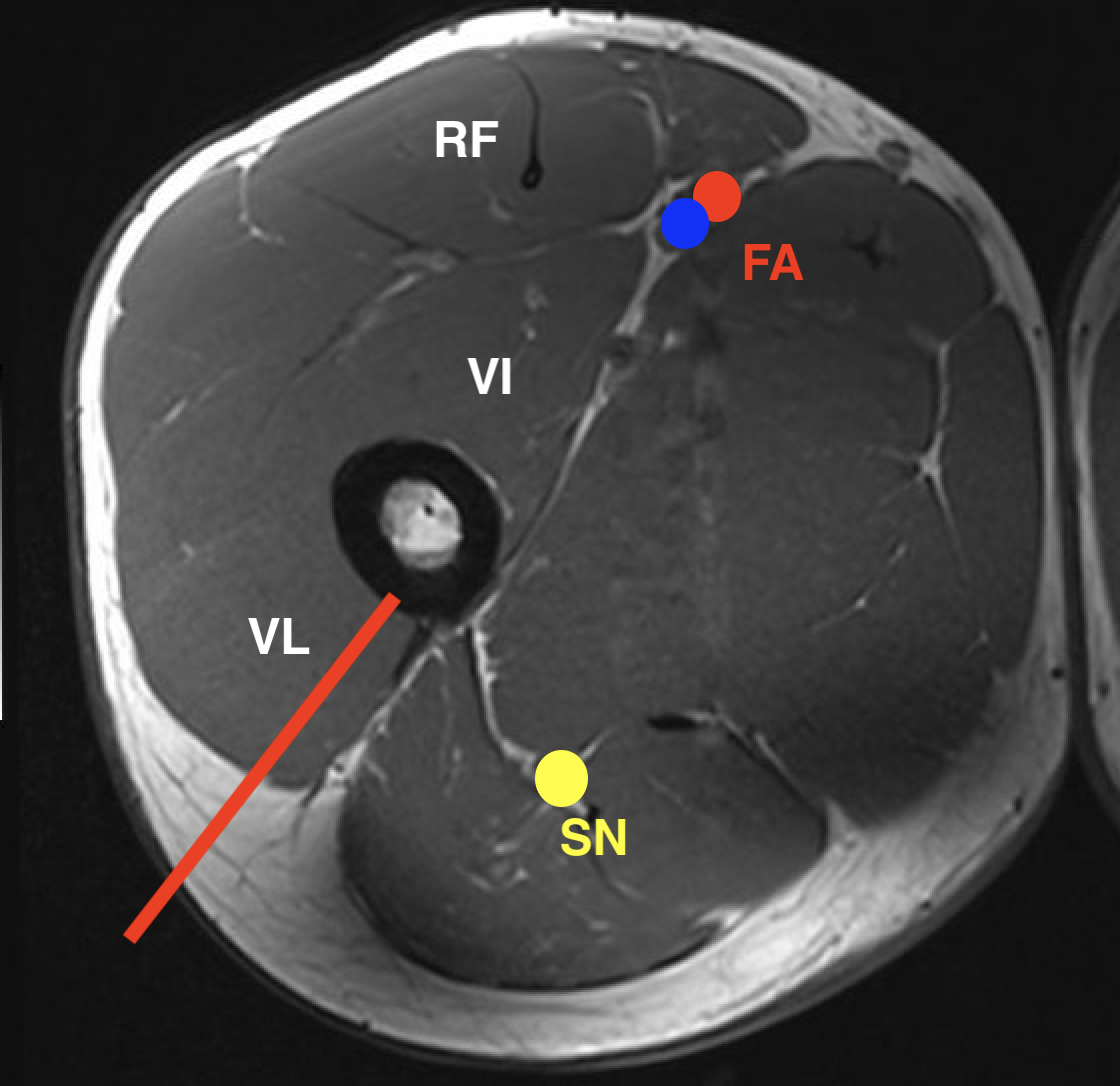

2.  Subtrochanteric / femoral shaft

- lateral approach

- aim anterior or posterior to lateral intermuscular septum depending on compartment

- avoid rectus femoris / vastus intermedius

- ok to resect part of vastus lateralis or biceps femoris